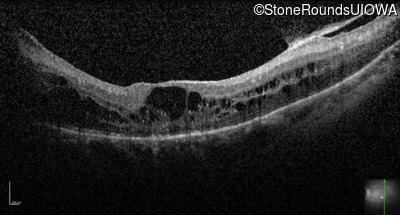

Optical Coherence Tomography - Right - 20/50 +2

Exemplar / OCT Stack